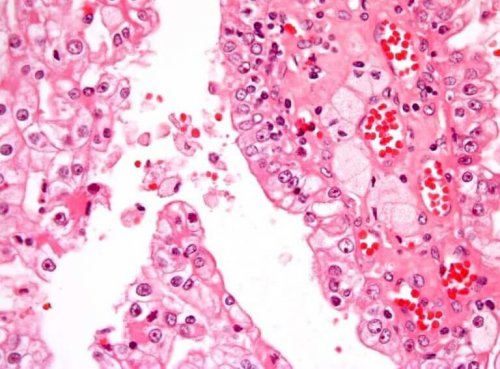

암은 악성 세포가 악성 세포가 정상 조직을 파괴하며 발생하는 질환으로 가장 흔한 소아 신장암은 빌름스 종양 또는 신아세포종이라고 불리며 미숙한 신아세포에서 시작된다. 한쪽 신장에서 발병해서 나머지 신장까지 전이되면 이를 양측성 종양이라고 한다.